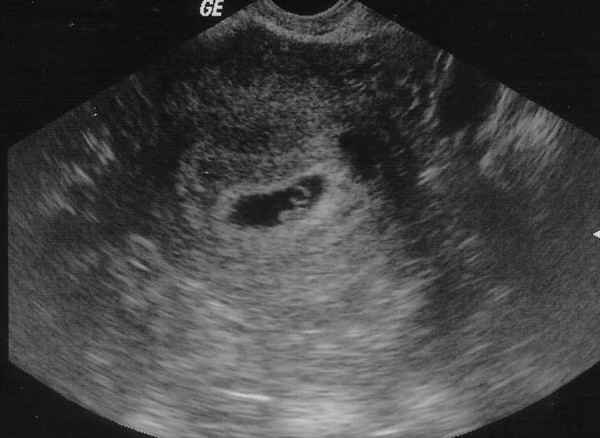

Каждый раз, закрывая глаза, я вижу маленькую горошину на мониторах аппарата УЗИ, а первое «фото» малыша я до сих пор храню у себя в блокноте. Зачем? Сама не знаю.